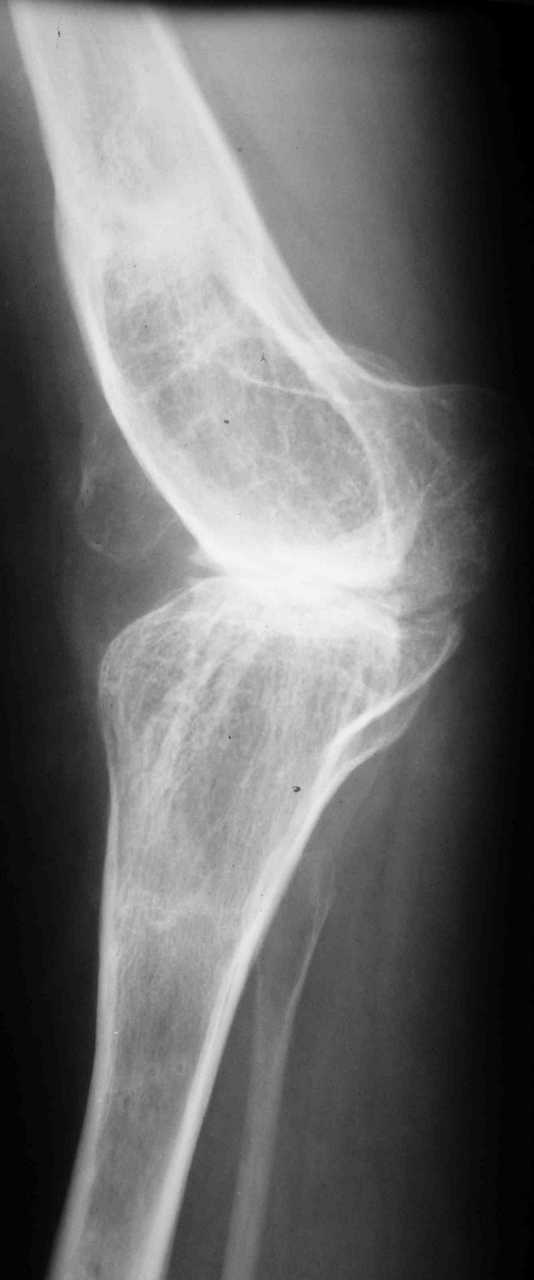

Уважаемые коллеги! К мне обратилась моя бывшая пациентка, 22 лет, с просьбой об эндопротезировнии коленного сустава. От артродеза категорически отказывается.DS: Врождённая аномалия развития левой нижней конечности. Состояние после удлинения бедра и голени (около 45 см). Варусная деформация шейки лев. бедра. Лев. коксартроз II ст. Лев. гонартроз III ст. Разгибательная контрактура лев. коленного сустава. Парез малоберцового нерва слева. Укорочение лев. н/конечности 1,5 см. Жалобы: на боли и нарушение функции в лев. коленном суставе.St. localis: ходит в брейсе с опорой на 1 трость. Относительная длина ног S – 1,5 см. Движения в лев. т/б суставе: сгиб. 70, разг. 180, привед. 60, отвед. 110, вн. рот. 20, нар. рот. 10; в лев. к/сус. пассивно: сгибание 0, разг. - 180+ 30; активно на переразгибание и из положения переразгибание на сгибание 2балла. Под нагрузкой вальгусно-рекурвационная деформация: клиничски на val. – 15-20, rec. - 30. Движения в лев. голеностопном суставе (акт./пас.): тыл. фл. 0/90, под. фл. 170, отвед. 10/15, прив. 25. Функция в других суставах не нарушена.Предполагаю, что наиболее лучшим вариантом будет двух этапное протезирование. На первом этапе – устранить антекурвацию на бедре аппаратом Илизарова; вторым этапом – протезирование – заднее-стабилизирующим протезом фирмы «Zimmer», т.к. маленькие размеры бедренной и большеберцовой костей.Возможны ли другие варианты лечения? Возможно ли одно этапное протезирование?Целесообразно ли в данном случае протезирование? Может быть не стоит идти «на поводу» у пациентки.Буду очень признателен всем, кто откликнется на мою просьбу.С уважением Игорь Атманский.

В настоящее время нет возможности сделать осевые снимки всей конечности. Это всё чем я раполагаю на сегодняшний день.

Трудно понять общую картину по "короткому" снимку в одной проекции. Желательно было бы увидеть нормальный снимок в двух проекциях, оптимально еще и снимок, захватывающий всю ось конечности от тазобедренного до голеностопного сустава.

Учитывая неоднозначность данного случая, такой снимок все равно надо делать.

Что касается самых общих соображений, то вызывает сомнения состоятельность боковых связок.